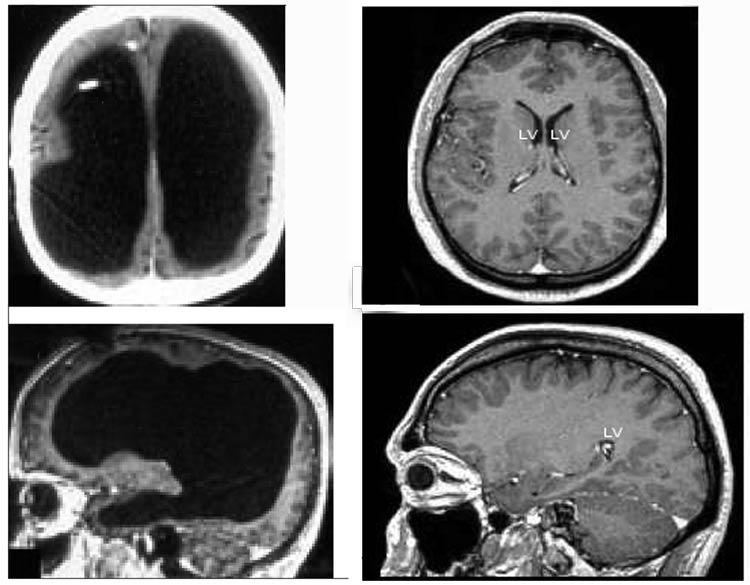

Fransada yaşayan bir adam, yaşadığı xəstəlik səbəbindən zaman ilə beyninin 90%-ini itirmiş olmasına baxmayaraq hər hansı bir əqli qüsuru olmadan yaşamağa davam edir.

Bundan sonra kimisə alçaltmaq üçün "beyinsiz" demək yerinə başqa bir söz düşünmənin vaxtı gəldi. Fransada yaşayan bir adam, yaşadığı xəstəlik səbəbindən beyninin 90%-lik qismini itirsə belə 75 IQ səviyyəsi ilə və əqli qüsuru olmadan yaşamağa davam edir.

Ölkəsində dövlət məmuru olaraq işləməyə davam edən adamın yaşadığı xəstəlik isə xalq arasında "beyində su toplanması" olaraq bilinən Hidrosefali-dir. Beynin tənəffüs mərkəzi kimi həyati bölmələrini əhatə edən qisminin təzyiqin təsiri ilə onurğa beyninə doğru sürüşməsi ilə yaranan bu problem, ani müdaxilə edilməsə təəsüff ki, ölümlə nəticələnir. Fransada yaşayan adam isə uşaq ikən yaşadığı bu problemə zamanında müdaxilə edildiyi üçün həyatda qalmağı bacarıb.